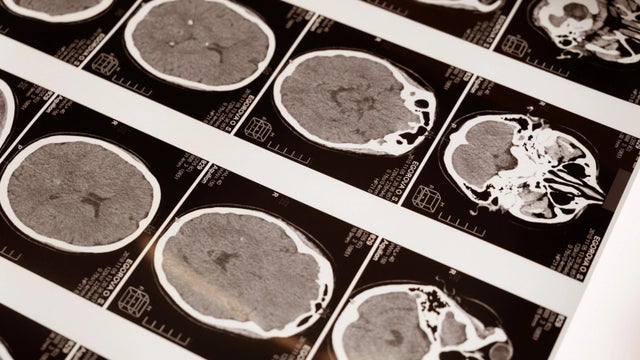

Através da neurociência cognitiva e do estudo do cérebro, podemos descobrir a importância de seus cuidados, a fim de evitar patologias futuras e intervir nelas quando necessário. Os últimos avanços no campo da neurociência cognitiva permitiram verificar a relevância do estabelecimento de planos de prevenção e educação neurológica, bem como estimulação e otimização de habilidades cognitivas. Através dessas neurociências de pós -graduação, os alunos são oferecidos aos conhecimentos e habilidades profissionais necessárias para expandir e/ou atualizar seus conhecimentos em uma das áreas com a maior demanda por pessoal qualificado nesse setor.

- Identifique as partes fundamentais dos neurônios e neuroglicos, classifique e descrevê -los. - Liste e descreva as diferentes partes do sistema nervoso central e periférico. - Aprenda as principais diferenças entre o hemisfério direito e esquerdo. - Analise o controle cerebral do movimento e as bases neurais da linguagem. - Localize as áreas do cérebro envolvidas em emoções e memória. - Descreva as características básicas da cor e sua fisiopatologia. - Conheça as principais estruturas do sistema nervoso. - relacionar estruturas neuroanatômicas com suas principais funções no nível do comportamento. - Identifique as principais técnicas de neuroimagem. - Estude as aplicações clínicas de cada técnica. - Conheça os principais aspectos e fundamentos da neuroanatomia humana. - Saiba quais são as principais técnicas de neuroimagem, bem como seu uso. - Estude as funções cognitivas, base neuropsicológica do comportamento humano. - Identifique os principais campos de pesquisa e aplicação da neurociência.